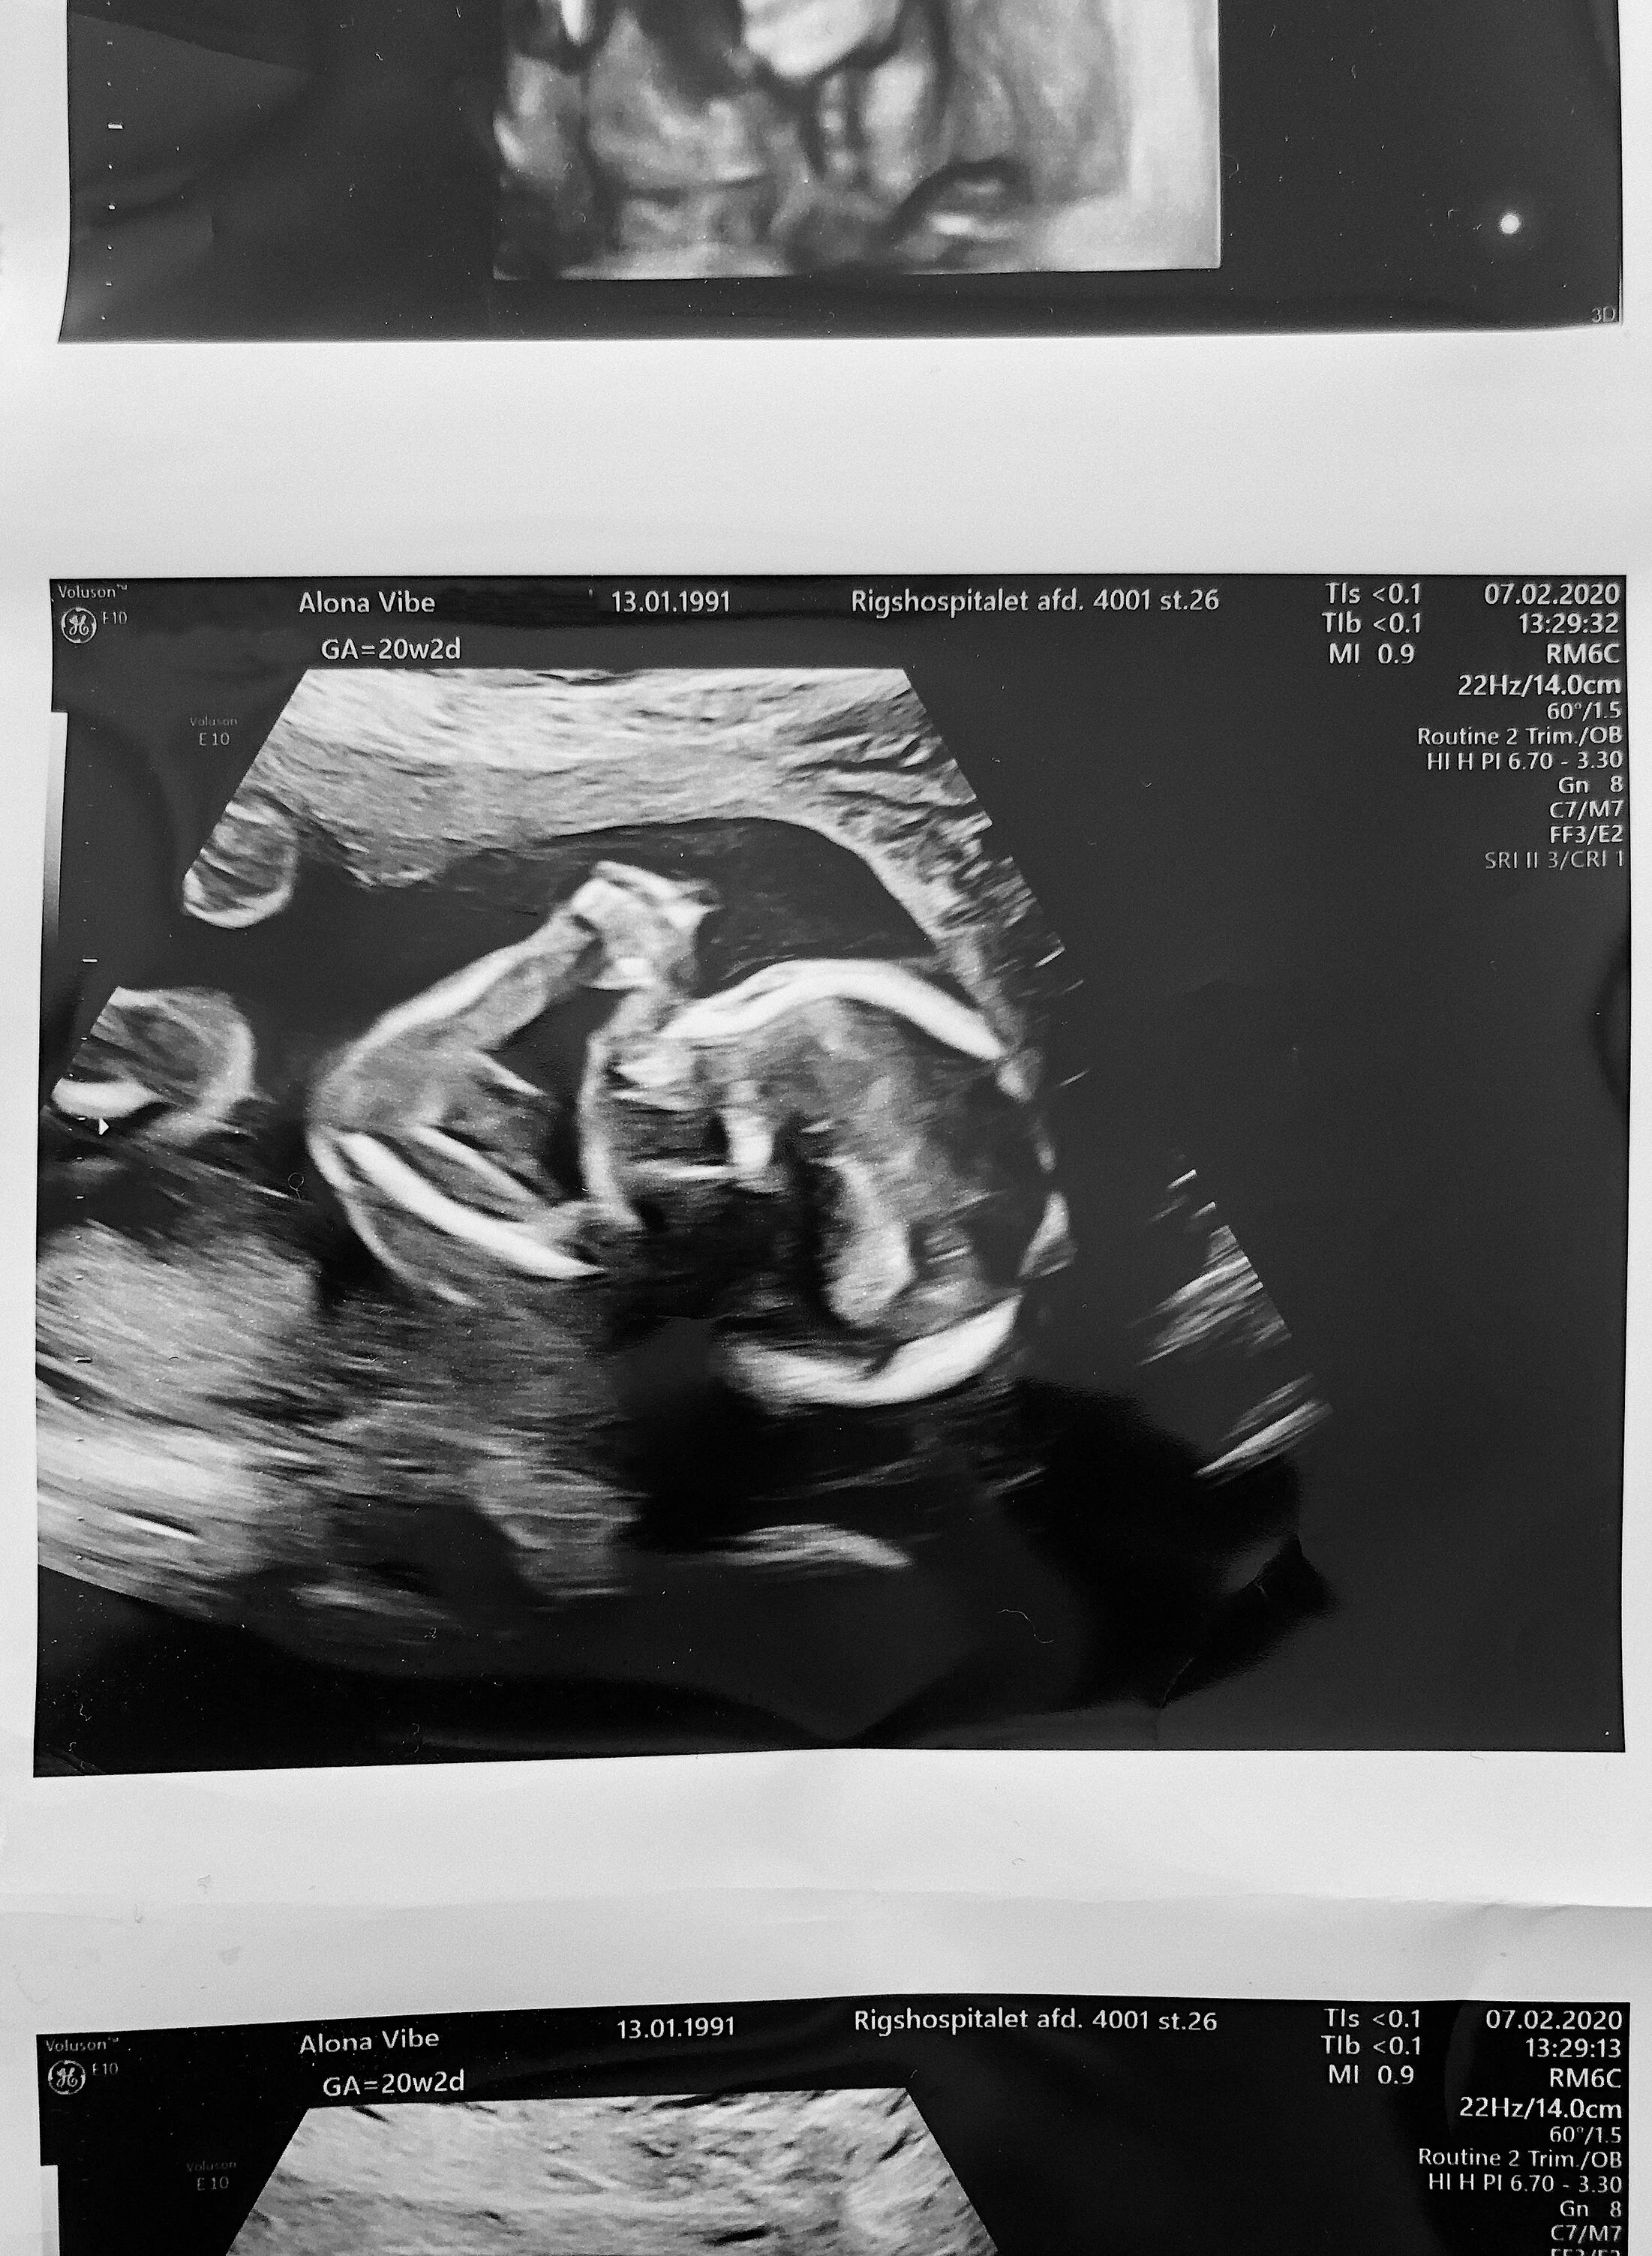

Scanningsbilleder fra misdannelsesscanningen i uge 20